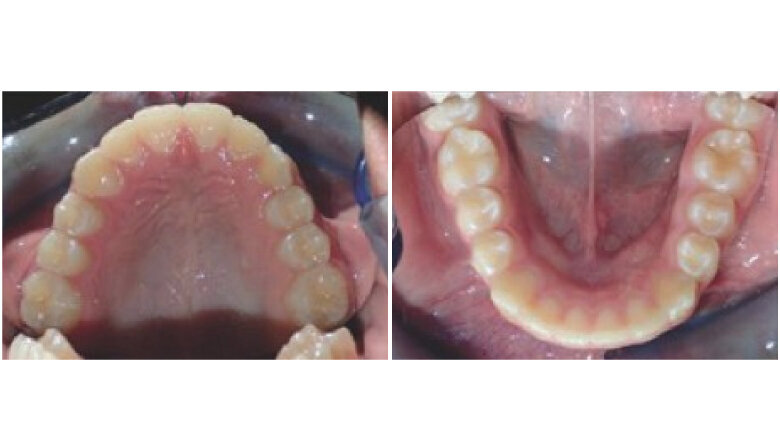

Initial Records

The patient is an 11 year 6 month old male with a chief concern of “overbite.” Diagnostic summary:

Class II, division 1 malocclusion (severe on the right, moderate on the left)

Deep overbite (moderate)

Moderate upper crowding

Mild lower crowding

The slightly retroclined upper incisors and flared lower incisors are consistent with dental compensations for a sagittal jaw discrepancy. The skeletal vertical dimension being within normal limits suggests that the deep bite is predominantly dental in nature.